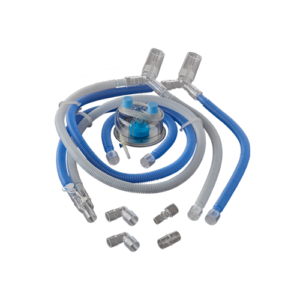

BC 585

Infant/Neonatal Breathing Circuit with Heated Wire for High Flow Oxygen Therapy